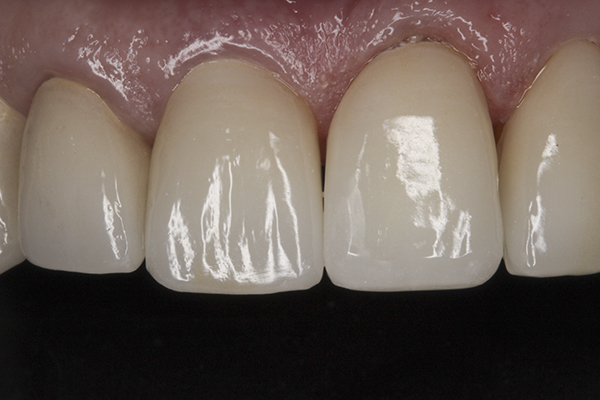

(38.) Postoperative right anterior, close-up view.

Figure 38

(39.) Postoperative anterior, close-up view.

Figure 39